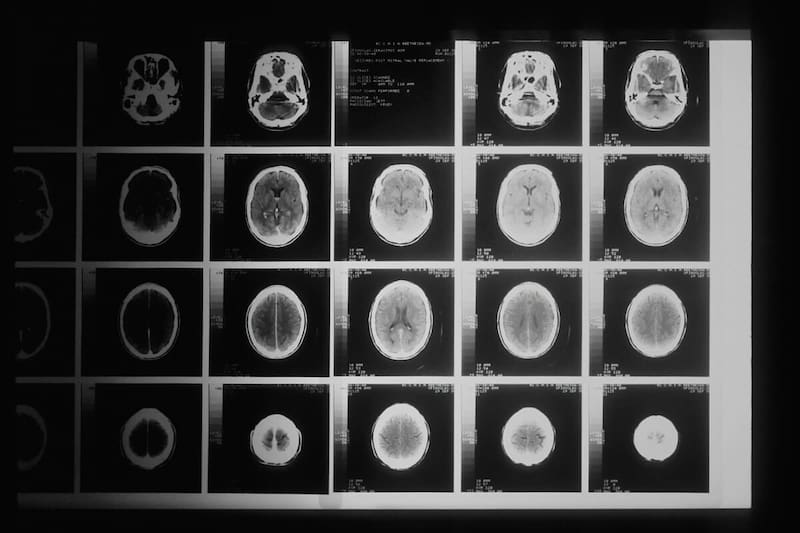

Un grupo de investigadores de la Universidad de Colorado decidió investigar los posibles efectos del edulcorante en el cerebro, específicamente, en la barrera hematoencefálica: un conjunto de células que se encarga de proteger al órgano y al sistema nervioso central de sustancias tóxicas que se encuentren en la sangre. Al mismo tiempo, también permite el paso de nutrientes.

Específicamente, los expertos realizaron el ejercicio de exponer las células de la barrera a niveles de eritritol similares a los que se encuentran en una bebida gaseosa sin azúcar. Esto les permitió observar una reacción en cadena de daño celular.

Los científicos denominan a esto estrés oxidativo, un proceso que cuando se desencadena inunda las células con moléculas dañinas y altamente reactivas, al mismo tiempo que reducen las defensas antioxidantes naturales del organismo.

En el experimento, este doble ataque dañó la capacidad de las células para funcionar correctamente y, en algunos casos, fue capaz de destruirla completamente.

Otro descubrimiento fue el efecto que tuvo el edulcorante sobre la capacidad que tienen los vasos sanguíneos para regular el flujo sanguíneo: estos actúan como controladores, es decir, se dilatan cuando los órganos requieren de más sangre y se estrechan cuando es el caso contrario.

El estudio reveló que el eritritol alteraba este sistema y causó preocupación en los científicos ya que, el resultado de la alteración de este proceso podrían ser vasos sanguíneos muy contraídos, lo que podría privar al cerebro del oxígeno y los nutrientes que requiere.